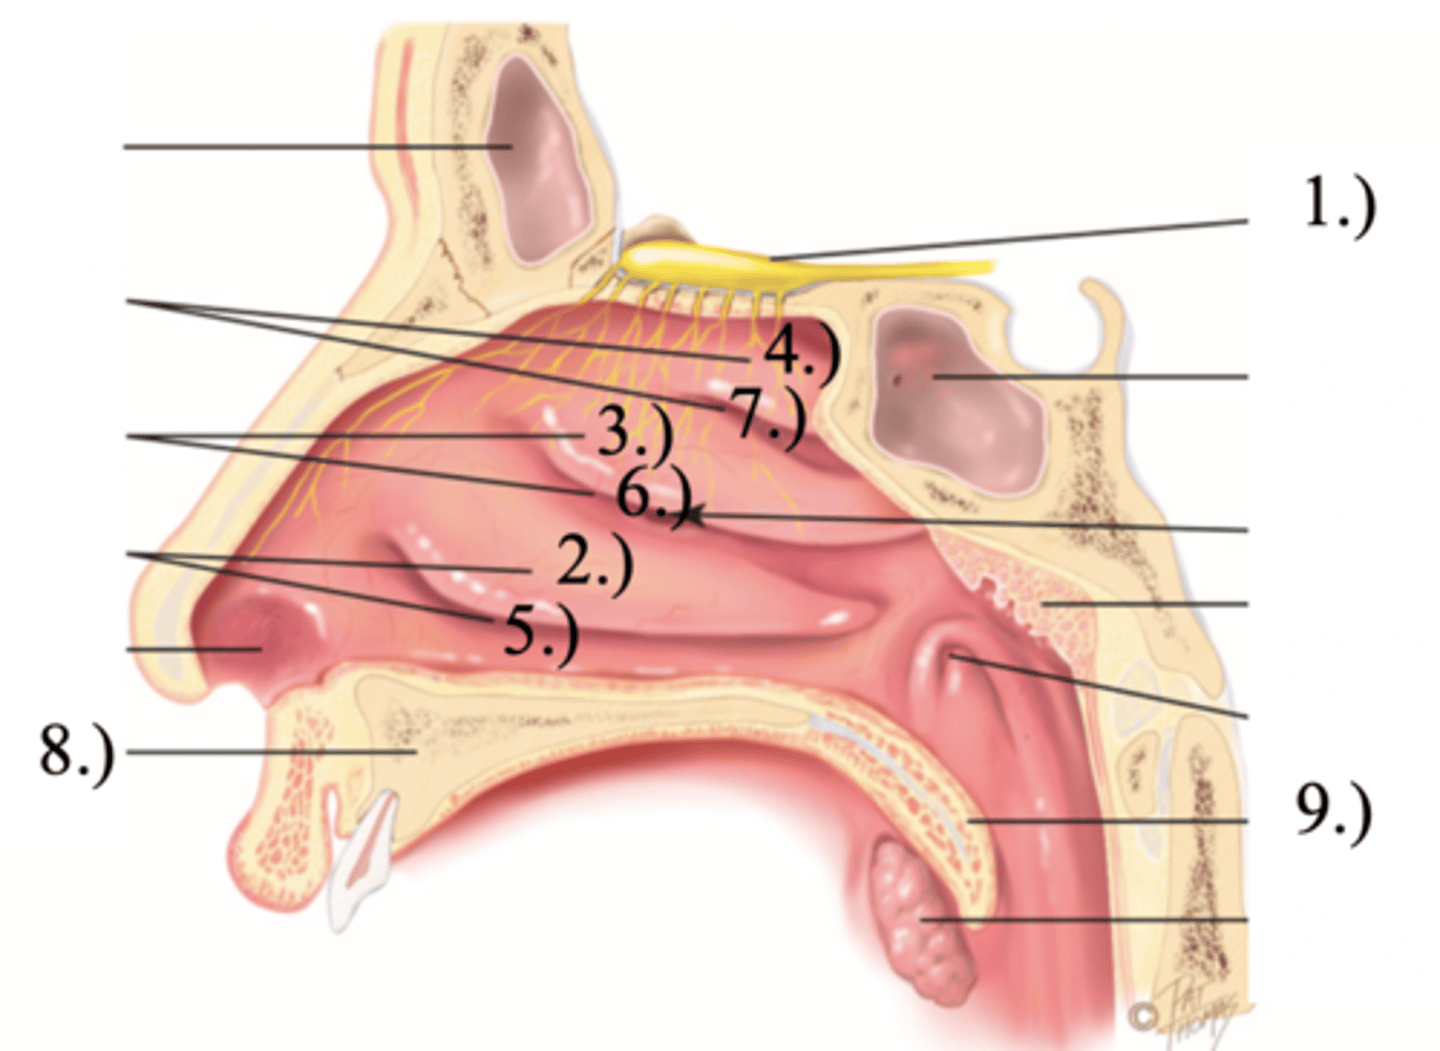

Turbinates (Conchae)

- There's an inferior, middle, and superior one (2.), 3.), 4.))

Olfactory Region

A dime-sized area at the top of each nasal cavity that houses sensors responsible for smell (1.))

Meatuses

- There's an inferior, middle, and superior one

(5.), 6.), 7.))

Anterior palate portion that is supported by the palatine processes of the maxillae and the palatine bones (8.))

Posterior palate portion, not supported by bone (9.))